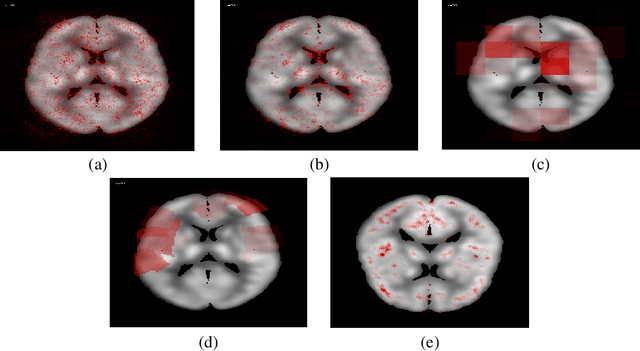

In recent days, Convolutional Neural Networks (CNN) have demonstrated impressive performance in medical image analysis. However, there is a lack of clear understanding of why and how the Convolutional Neural Network performs so well for image analysis task. How CNN analyzes an image and discriminates among samples of different classes are usually considered as non-transparent. As a result, it becomes difficult to apply CNN based approaches in clinical procedures and automated disease diagnosis systems. In this paper, we consider this issue and work on visualizing and understanding the decision of Convolutional Neural Network for Alzheimer's Disease (AD) Diagnosis. We develop a 3D deep convolutional neural network for AD diagnosis using brain PET scans and propose using five visualizations techniques - Sensitivity Analysis (Backpropagation), Guided Backpropagation, Occlusion, Brain Area Occlusion, and Layer-wise Relevance Propagation (LRP) to understand the decision of the CNN by highlighting the relevant areas in the PET data.